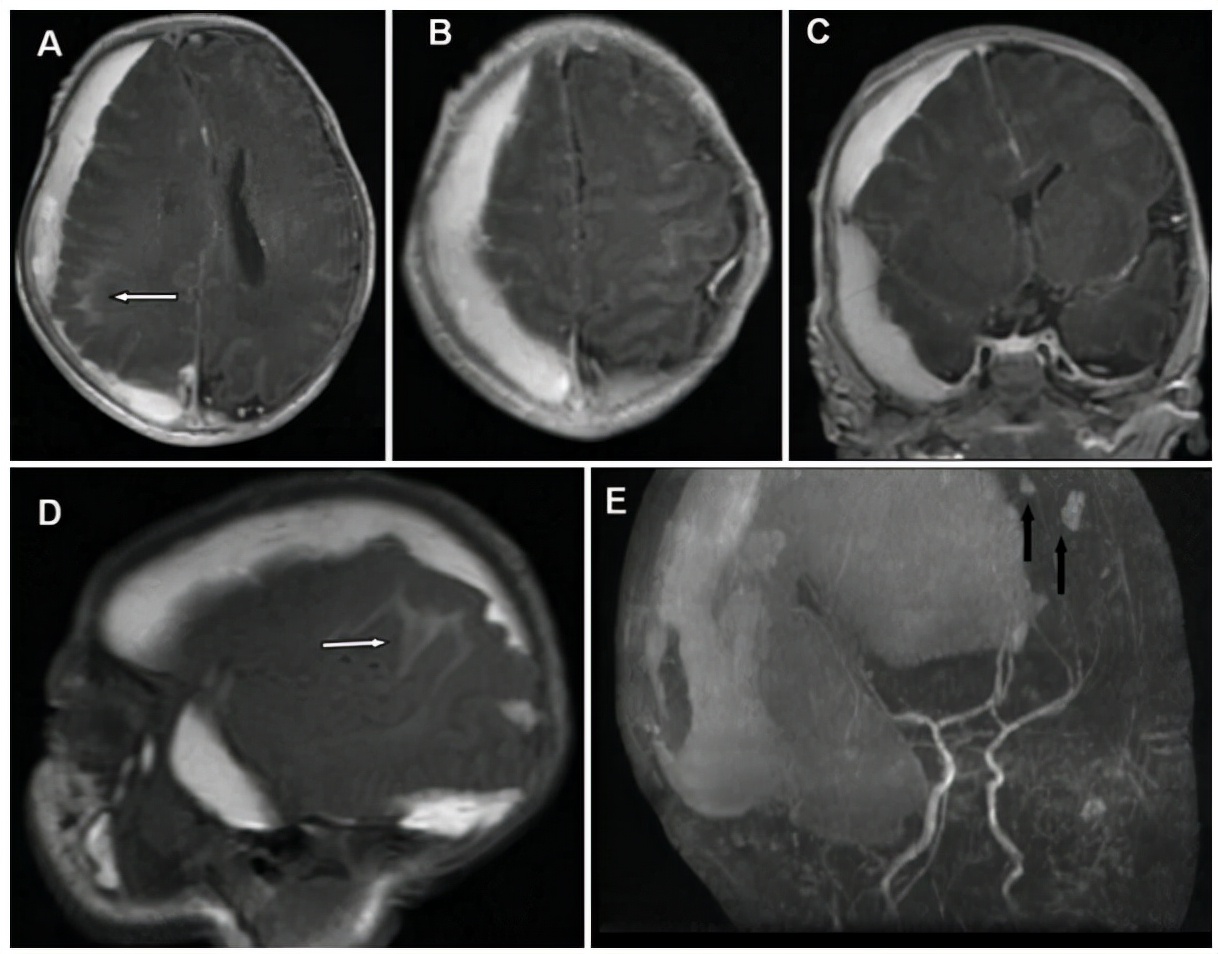

Alan出生后不久又发现凝血功能障碍。异常的凝血功能被认为是由于血肿扩大消耗了凝血因子;因此,除服用维生素k外,未进行任何促凝治疗。弓形虫、风疹、巨细胞病毒和疱疹(TORCH)研究以及血液和尿液培养均为阴性。产后大脑MR成像研究证实右侧半球脑血肿(最大厚度15 mm)较大,造成肿块效应和4.4 mm中线移位。右侧脑室受压和左脑室扩大也很明显,右顶叶有局限性SAH(蛛网膜下腔出血),左额叶前部有2处小挫伤(图2)。磁共振血管造影也排除血管畸形。

图2:新生儿(出生后第1周)脑部T1加权轴向(A和B)、冠状(C)和矢状(D)磁共振图像,以及3D血管造影磁共振图像(E),确认右侧脑血肿(厚度15 mm)的存在,导致质量效应,随后中线移位4.4 mm,右侧脑室受压。注意顶叶SAH(白色箭头)和额叶挫伤(黑色箭头)